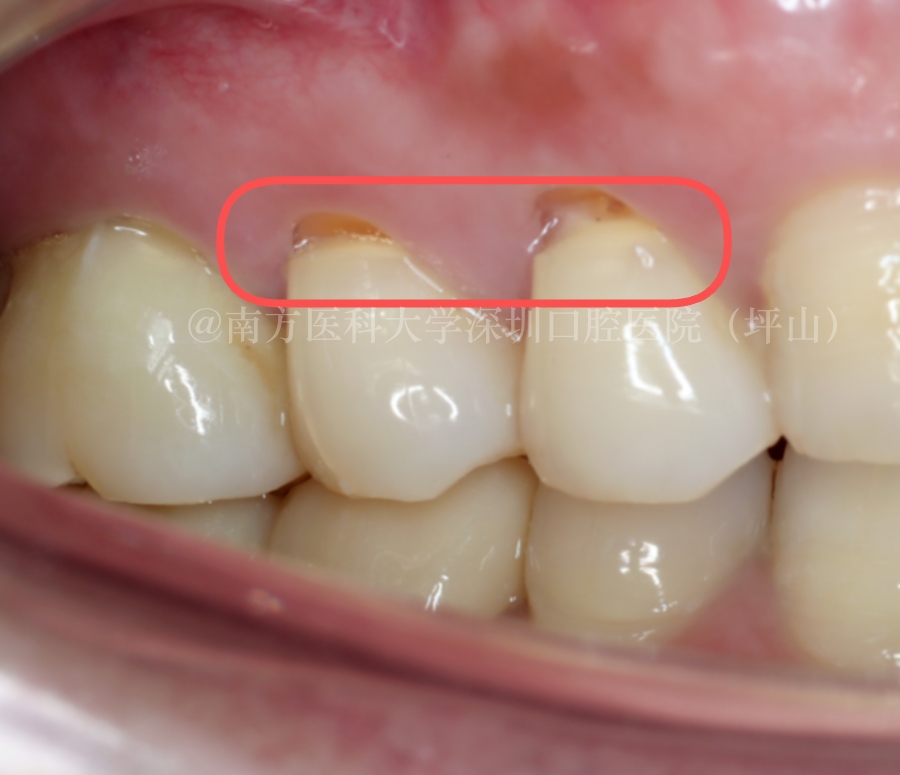

在牙齿的颈部位置出现小的缺损,被称为“楔状缺损”。

一般认为,楔状缺损与刷牙方式不正确有关。很多人都有刷牙太暴力或者横向刷牙的问题,一旦造成楔状缺损,牙齿很容易敏感、甚至疼痛,治疗的话,一般用树脂充填就可以了。